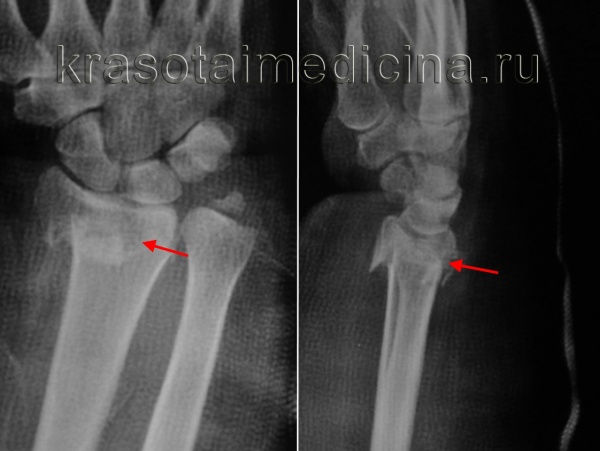

Пациент Х. Травма в быту, упал на бордюрный камень, получил закрытый перелом обеих костей правого предплечья со смещением, разрывом дистального радио-ульнарного сочленения. Обратился в РТП, выполнены рентгенограммы. Наложена гипсовая лонгетная повязка.

Пациент обратился в К+31, учитывая характер перелома пациенту предложено оперативное вмешательство.

Выполнен остеосинтез обеих костей правого предплечья метафизарными пластинами 3,5 мм, фиксация дистального радио-ульнарного сочленения винтом.

Реннтгенограммы после операции.

Рентгенография лучезапястного сустава. Перелом дистального метаэпифиза лучевой кости со смещением отломков.